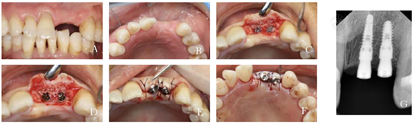

(2)即刻种植一期手术过程:①术前采集患者静脉血9 ml制备1 U浓缩生长因子(concentrate growth factors,CGF),压制成膜,备用。②笑气/氧气吸入镇静下局部浸润麻醉,微创拔除21,探查牙槽窝骨壁完整。③沿22牙槽嵴顶黏膜偏腭侧切口,翻瓣,球钻偏腭侧定位,逐级备洞,21植入DIO 3.8 mm×12.0 mm种植体,植入扭矩为15 N·cm,旋入愈合帽,22植入DIO 3.8 mm×10.0 mm种植体,植入扭矩为35 N·cm,旋入愈合帽。④21种植体颈部跳跃间隙及22唇侧颈部植入Bio-oss骨粉,覆盖1 U CGF膜。⑤21拔牙窝腭侧近中作三角弧形切口,贴骨膜锐性分离半厚黏膜,形成带蒂结缔组织瓣,蒂在拔牙窝腭侧远中。⑥21、22之间唇侧龈缘做斜行切口,旋转腭侧与唇侧结缔组织瓣吻合,无张力对位良好,5-0可吸收缝线严密缝合创口(图3)。

(3)术后复查:术后2周、1个月、2个月、5个月复查,21、22术区黏膜愈合良好,X线片显示种植体周围骨结合良好(图4)。

(4)种植二期手术过程:种植一期手术6个月后,0.5%碘伏消毒21、22术区,局部浸润麻醉下,沿21、22牙槽嵴顶偏腭侧黏膜作近远中向切口,全层翻瓣,见愈合帽上方部分骨质覆盖,去除愈合帽表面多余硬组织,取下愈合帽,安装N 4.1 mm×5.0 mm愈合基台,牙龈修整、黏膜瓣复位,5-0可吸收缝线缝合创口(图5)。